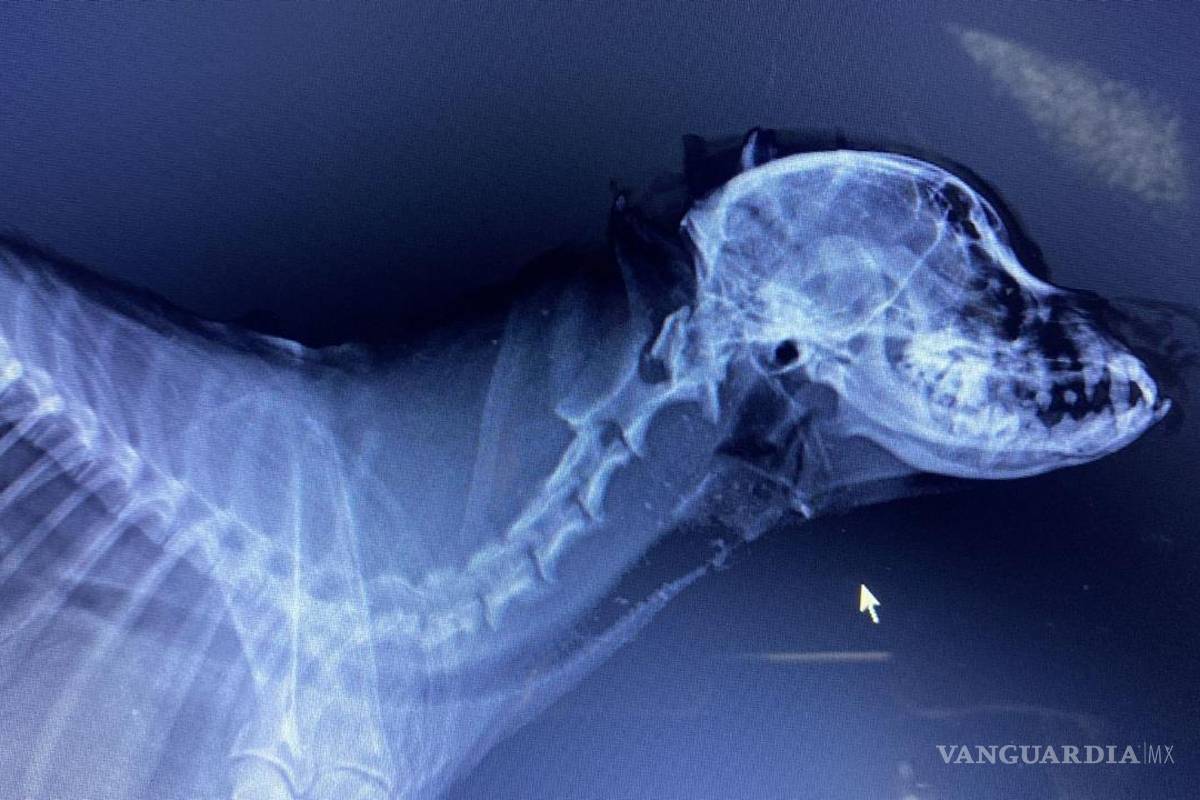

FUERON VARIAS FRACTURAS LAS QUE SE DETECTARON POR ESPECIALISTAS EN EL CRÁNEO DE PAPUCHO

Después de que una vecina de la colonia Emiliano Zapata golpeara en diversas ocasiones a Papucho con un palo de golf, este fue llevado a una veterinaria con apoyo de la Fundación Taraji A.C., especialistas en el tema afirman que la mascota sufrió diversos golpes que causaron la inflamación de su cerebro, por lo tanto continúa paralizado.

“Como conclusión a la imagen en pocas palabras se ve que fueron varios impactos, no solo uno, asi lo demuestran los rayos x” dijo el veterinario a Oscar Zamora Bustos su dueño.

Expuso que tiene al menos golpe en el maxilar superior, en cráneo y en el axis, a raíz de esto tiene toda la cabeza interna inflamada, desde el cerebro hasta el esófago.